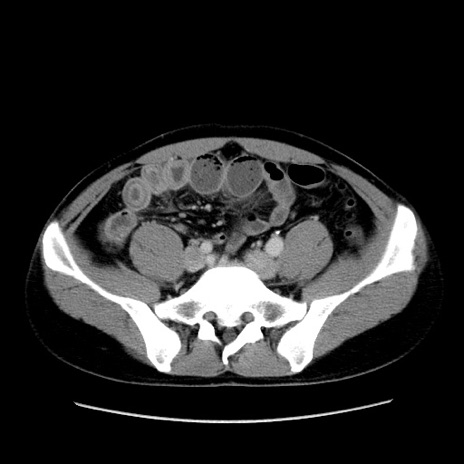

症例4(横断像)

【症例】30歳代男性

【主訴】腹痛、嘔吐

【現病歴】昨晩から突然の腹痛あり、その後嘔吐、軟便も出現。腹痛が改善しないため救急搬送となる。2日前にしめ鯖の食事歴あり。

【身体所見】意識清明、苦悶様、BP 135/90mmHg、BT 35.7℃、腹部:平坦、やや硬、心窩部〜臍部に自発痛、圧痛あり、筋性防御+、反跳痛-

【データ】WBC 8100、CRP 0.57